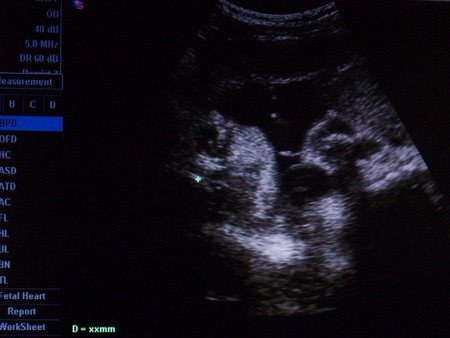

может, плохо видно, но это Лева выглядывает)):